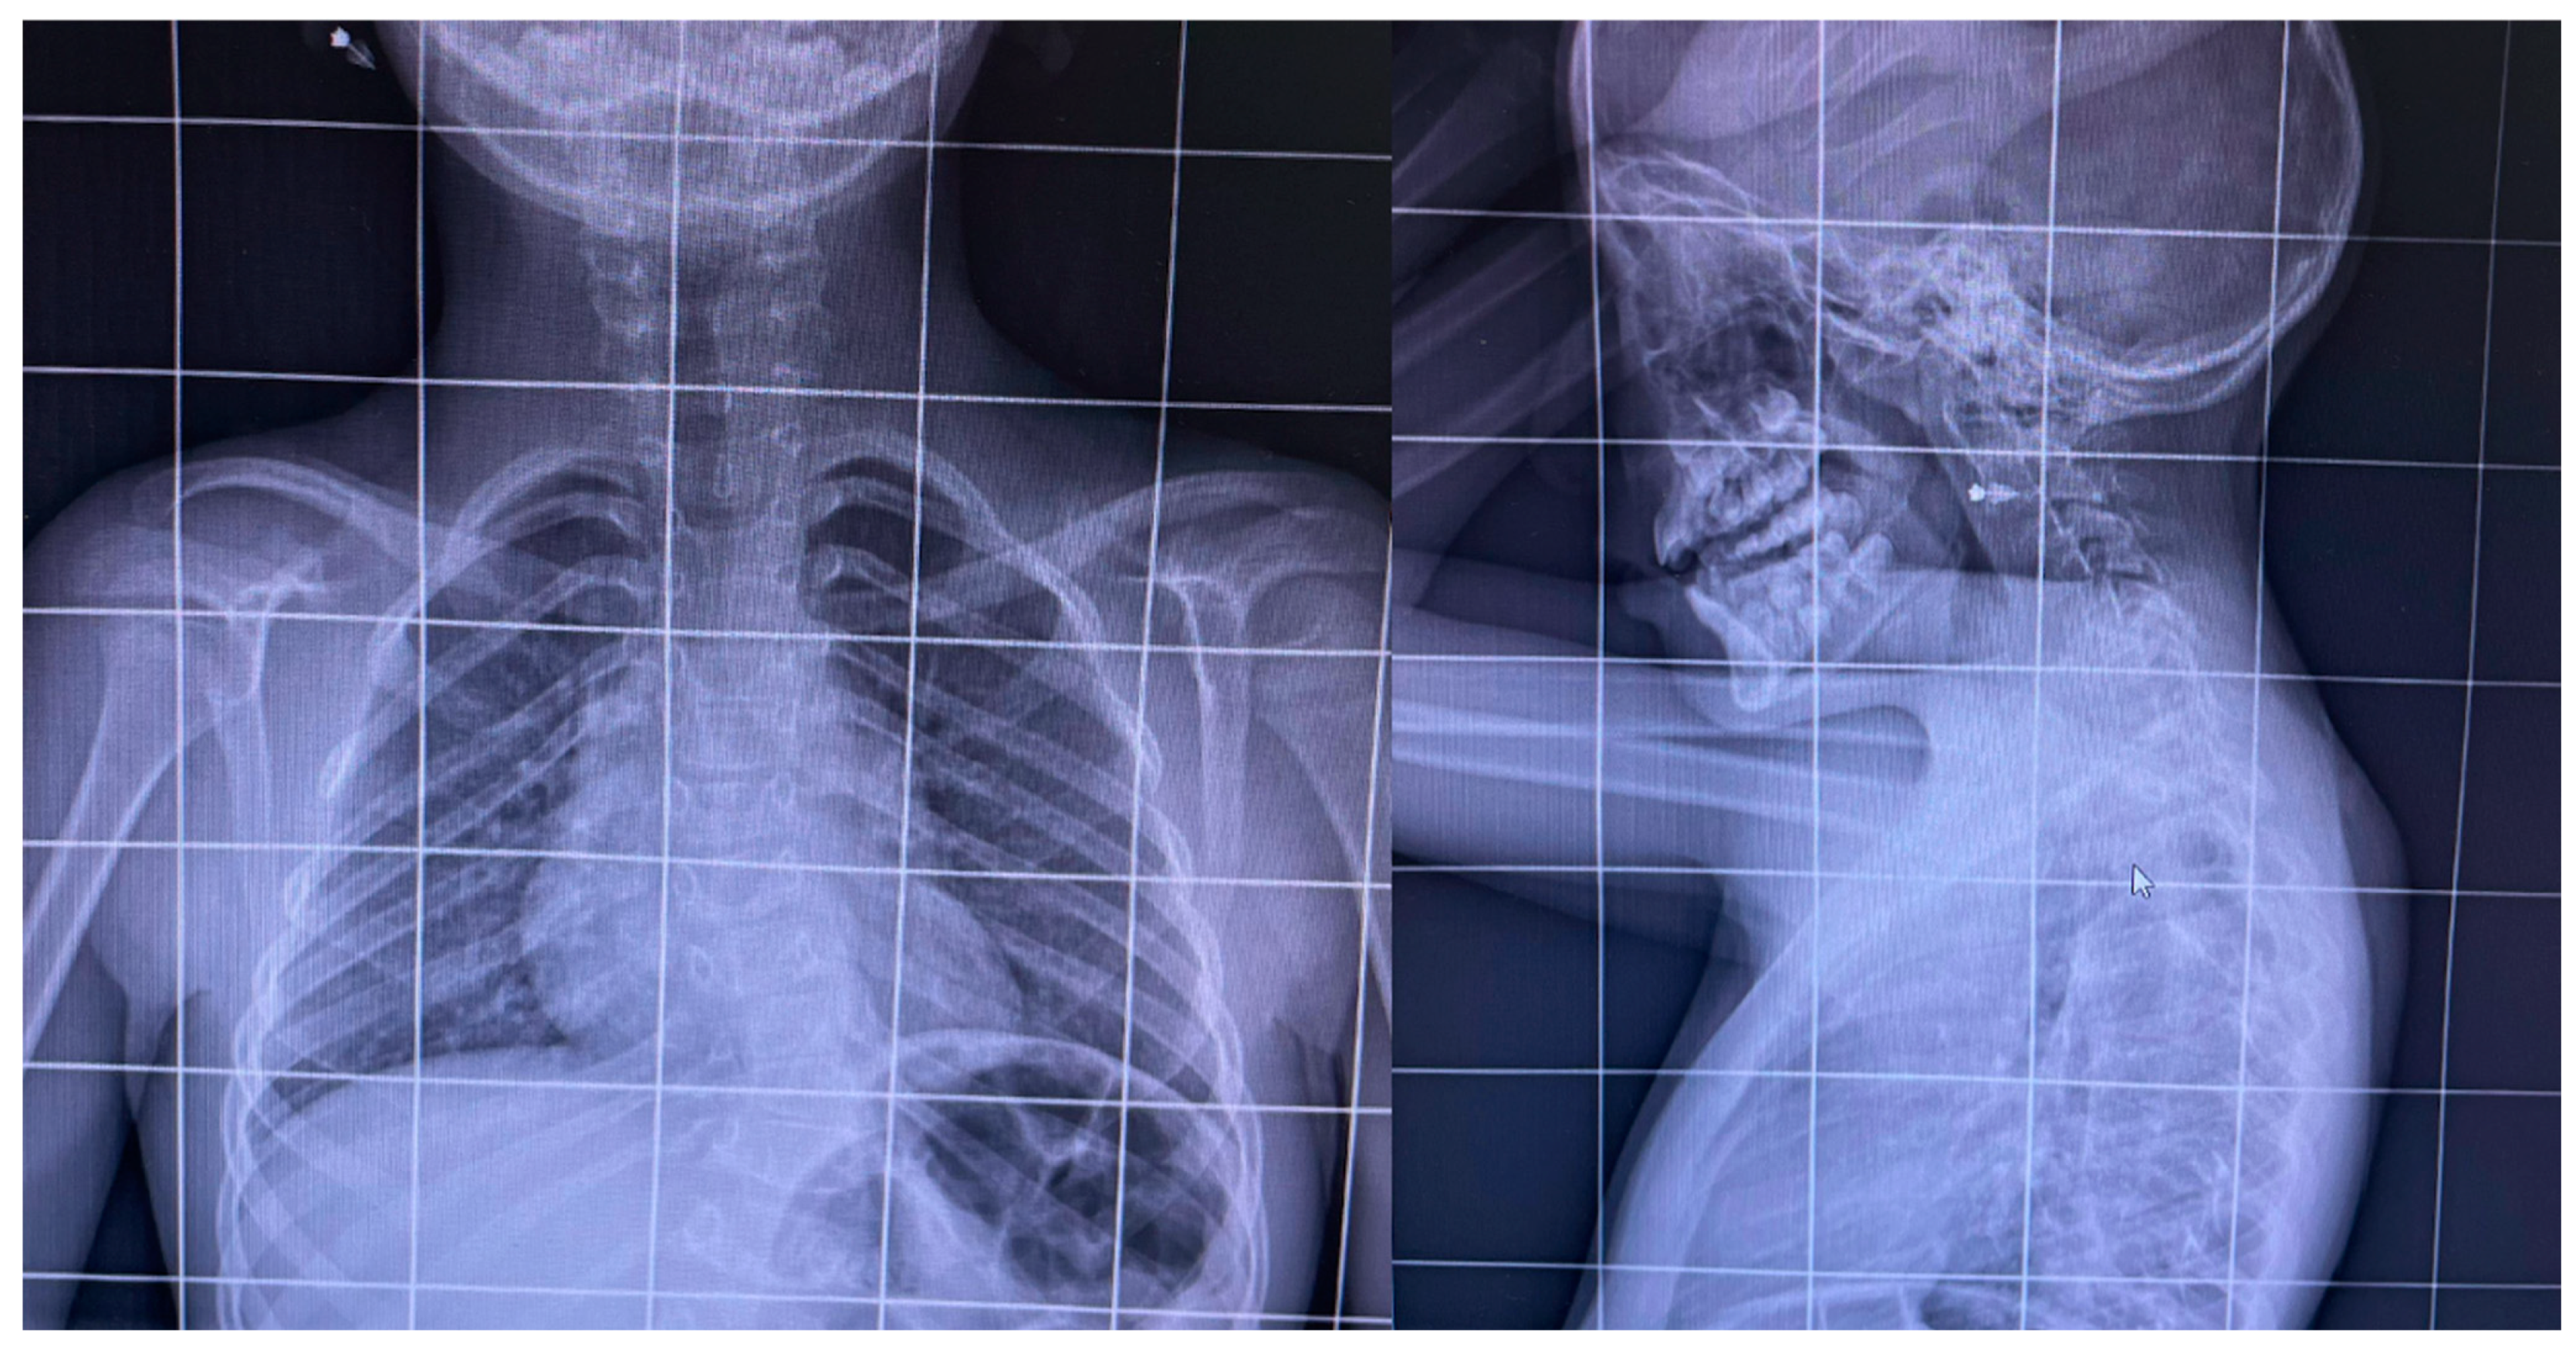

The Synergistic Effects of Incobotulinum Toxin and Physiotherapy in a Rare Case of Paraparesis in a 7-Year-Old Affected by Klippel–Feil Syndrome Related to an MYH3 Gene Mutation: A Case Report

2. Case Report